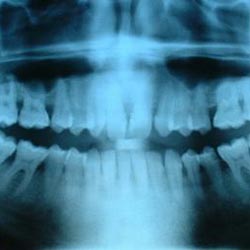

Teeth Facts

Check out our range of fun tooth facts for kids. Learn about different types of teeth, how many you have, what they do and much more. Read on and enjoy a variety of interesting information about human teeth.